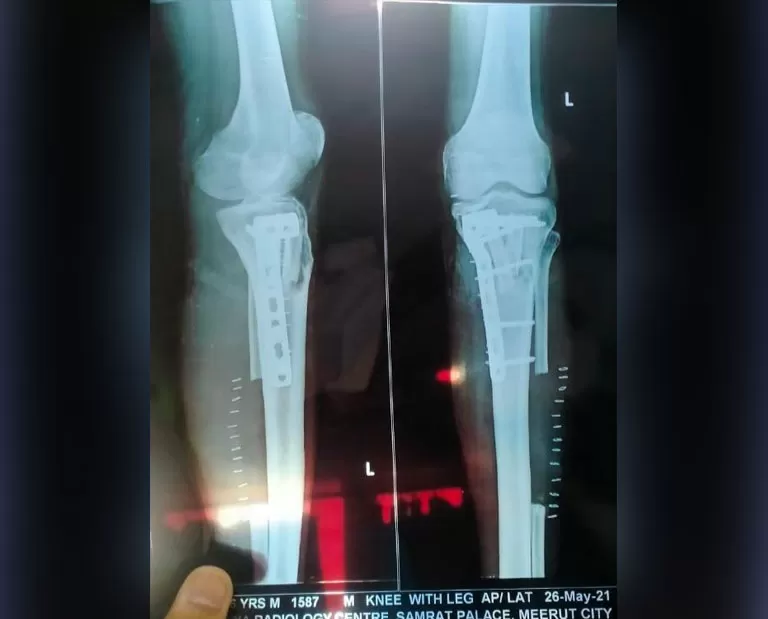

Mr. Rohtash

Name: Mr. Rohtash

Date of Operation: 17 Mar 2021

Age: 45 Years

Mobile No: 98885 35038